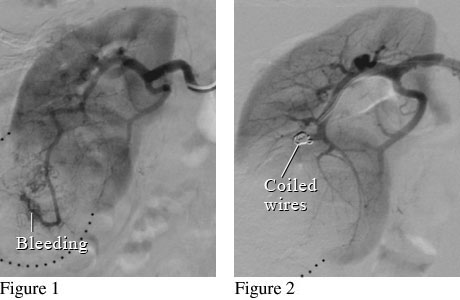

Angiogram of a Renal Mass

Angiogram image of a renal mass

Figure 1 shows a kidney with a large mass that is bleeding. Figure 2 shows small coiled wires that have been placed in the artery to block the bleeding.